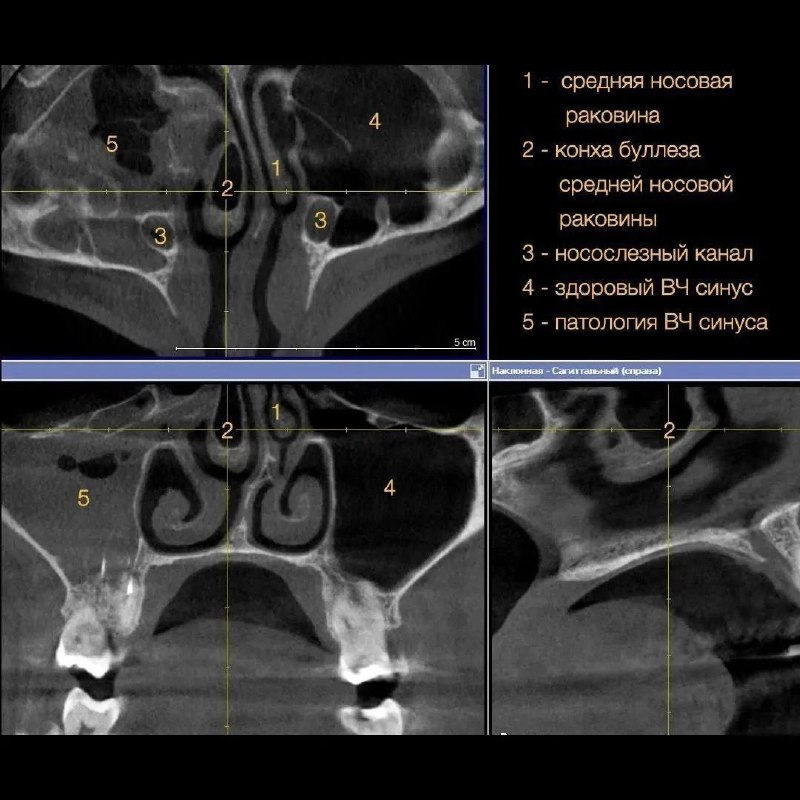

Функции носовых раковин

Функции носовых раковин 106 фото